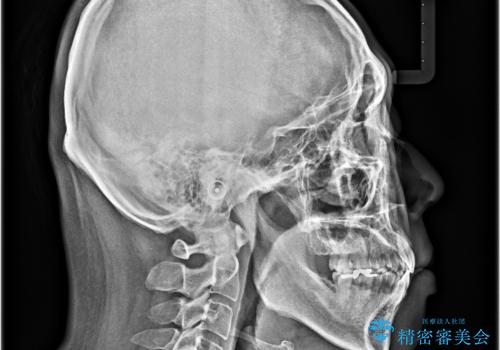

口が閉じられない 抜歯矯正で前歯の突出感を改善

2年から2年半の治療期間を想定しており、予定通りの期間で無事に終了することができました。

唇や顎先に力を入れないなくてもスムーズに唇を閉じることができるようになりました。